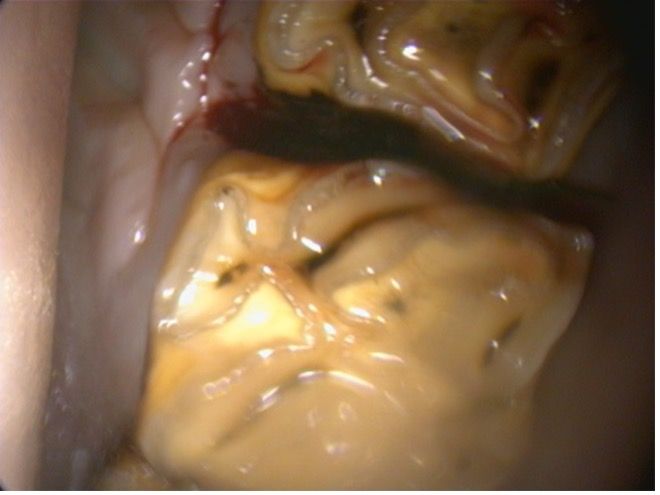

Diastemata is an interdental space between 2 adjacent cheek teeth and can be present in up to 4% of horses. Caudal mandibular cheek teeth are most involved, particularly the interdental (interproximal) spaces between molars 09s and 10s and between 10s and 11s. The presence of space between the teeth usually leads to the accumulation of food material and the development of periodontal disease (Figure 1A). In advanced cases, this can lead to alveolar bone resorption or the formation of an oronasal fistula. Periodontal disease is a painful condition, and quidding is a common associated clinical sign.4

For valve diastemata (where the space is narrower occlusally), one treatment option is to widen the space with a burr to allow for better evacuation of the trapped food material, and this has proved successful in selected cases. Other treatment options for diastemata include flushing the space using a periodontal unit (Figure 1B) and packing the space with dental fillers. In more severe cases, exodontia of one of the teeth may be needed.5